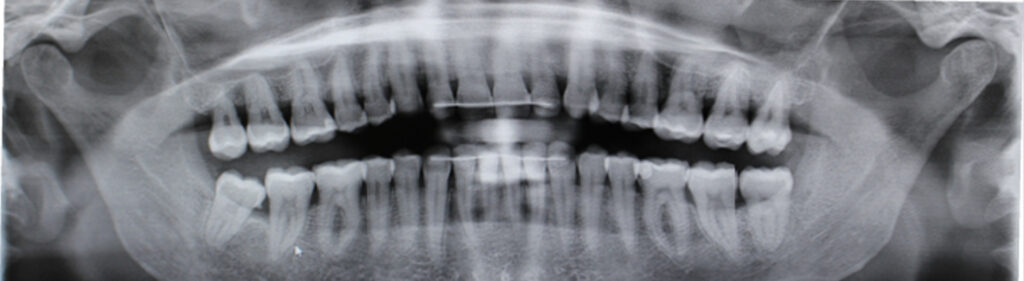

This article describes a treatment with spark aligners performed in a 52-year-old patient, who presented at the time of consultation with an increased overbite, moderate crowding in both arches, gingival smile and a clear alteration in the color of the enamel due to environmental factors.

At the end of the primary treatment plan the patient returns to the office and we can see that, although the vertical plan has been favored thanks to the planned movements, the midlines are centered, and the crowding has improved notably and with it the periodontal status of the patient.

After 8 months of the primary treatment plan and the refinement, it was possible to observe a fulfillment of the objectives demanded by the patient and clinically marked at the time of the initial diagnosis.